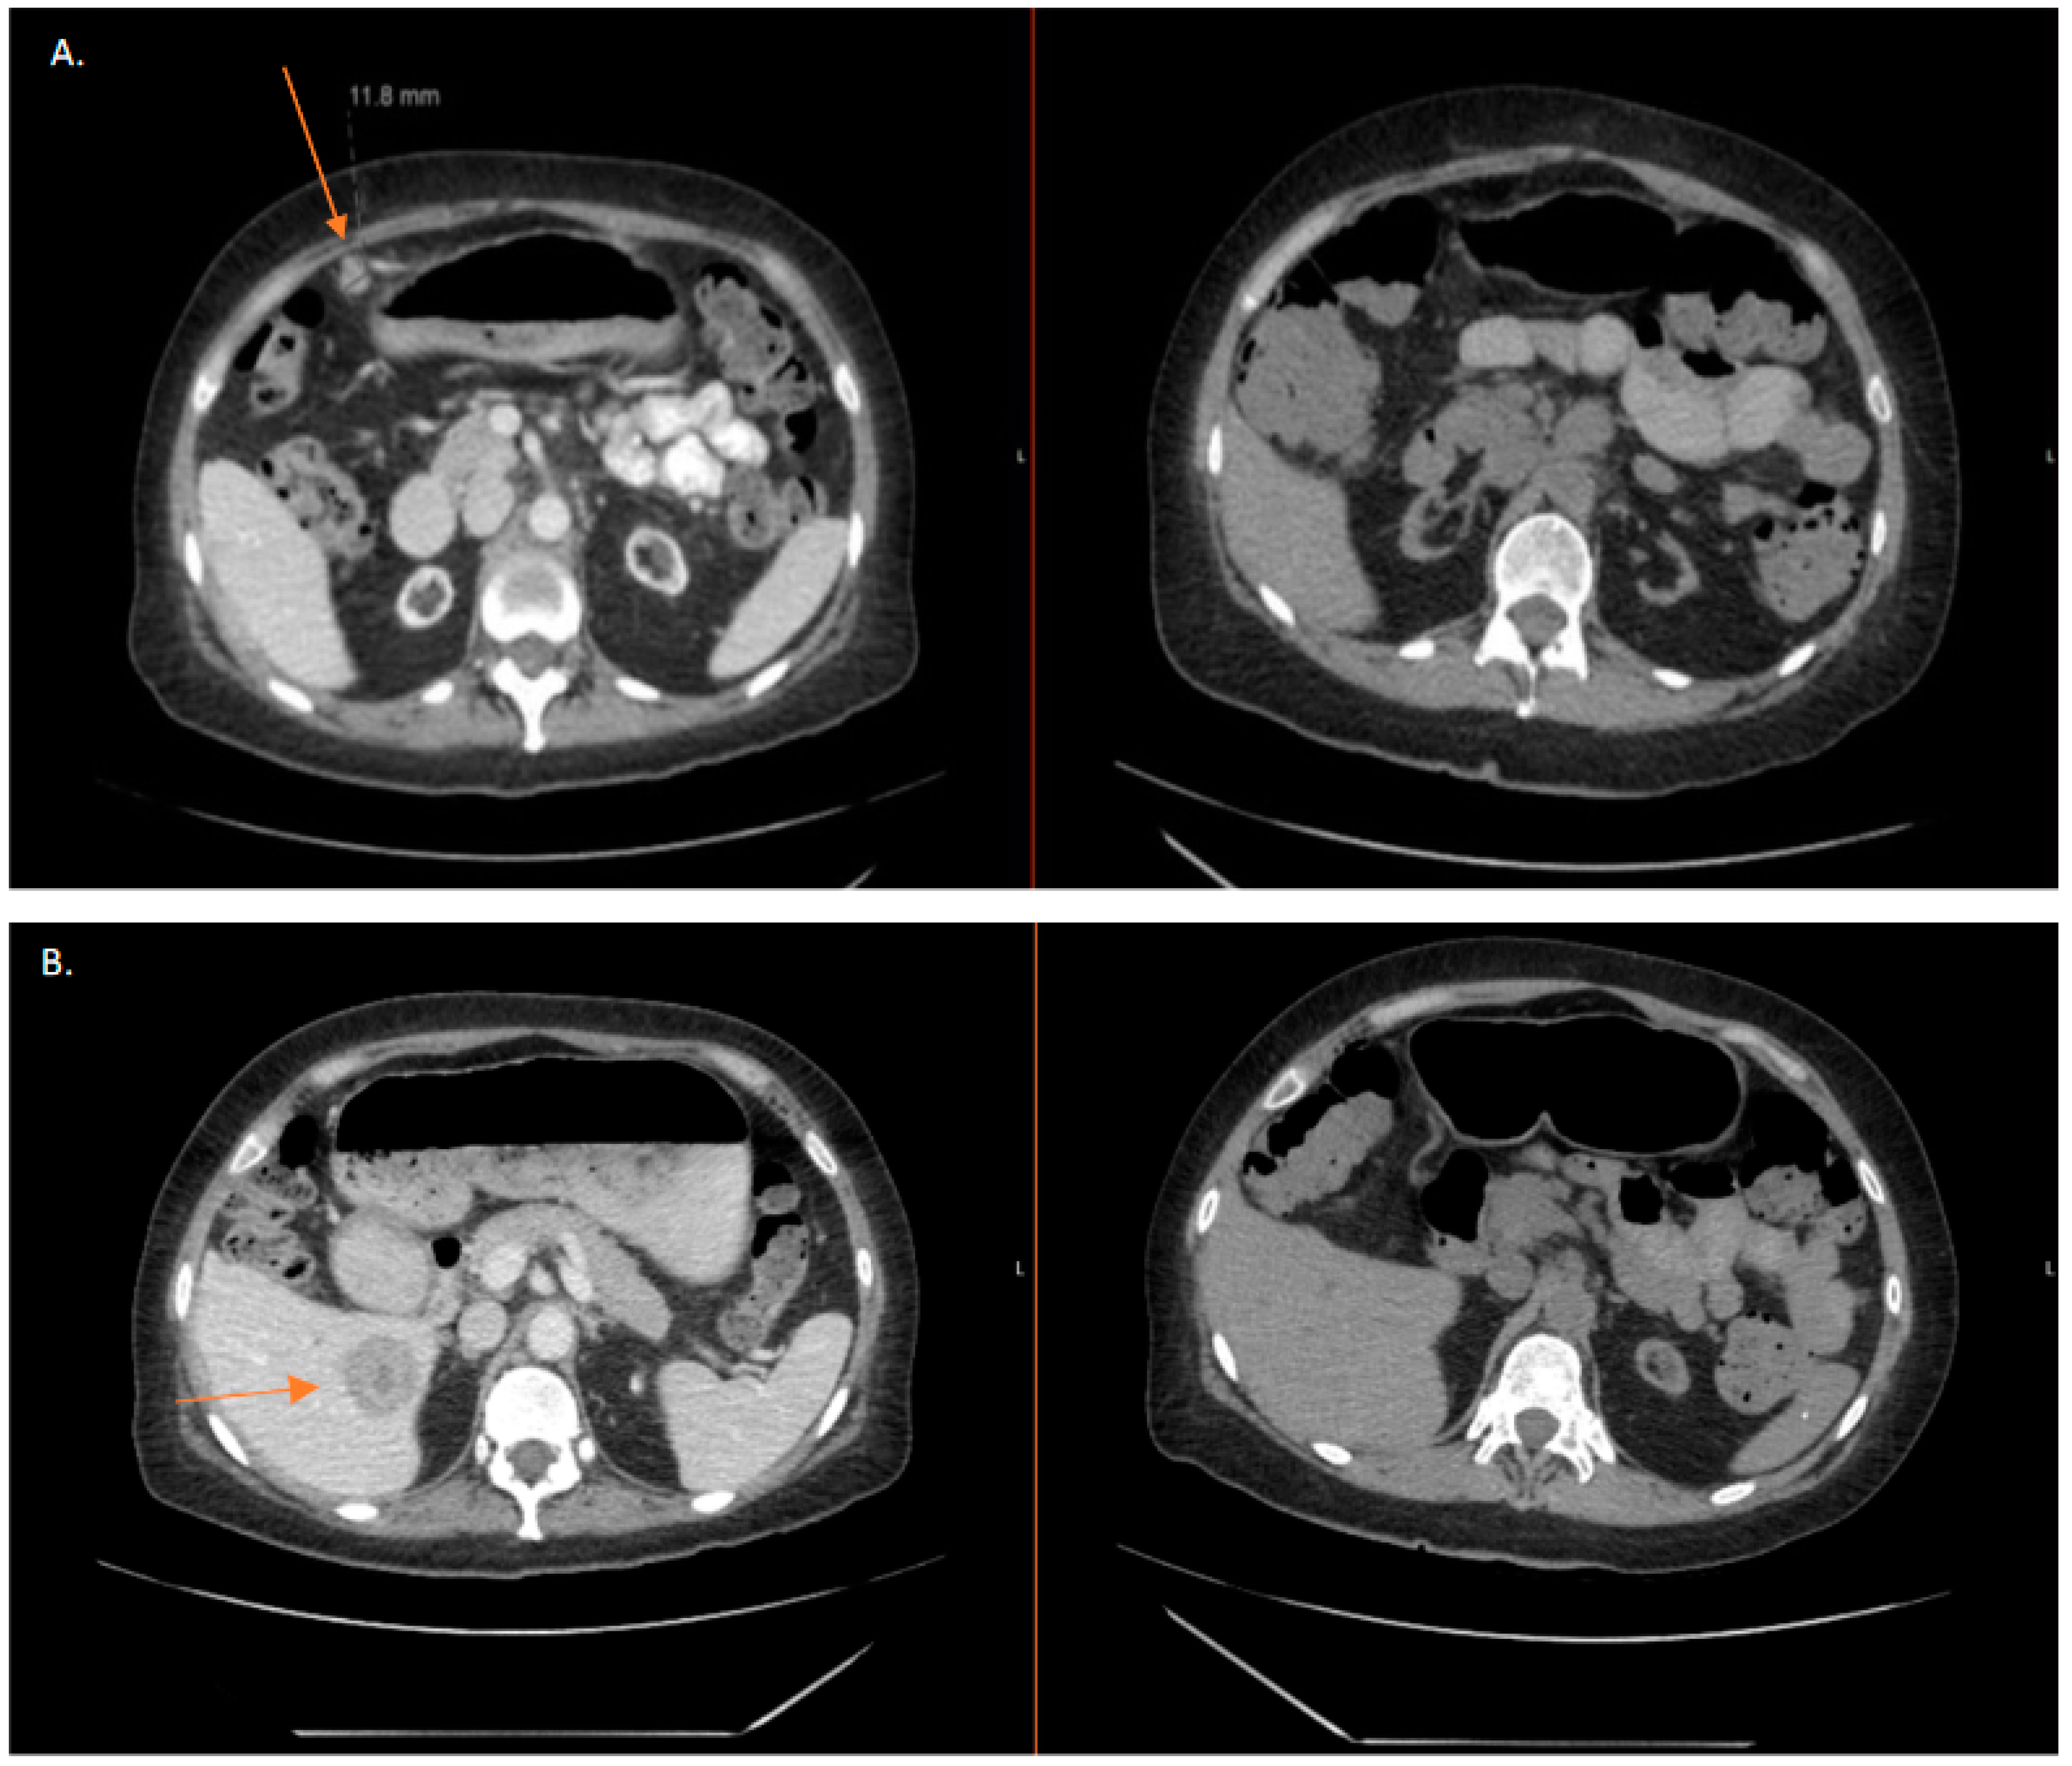

2.7. Compassionate Treatment with Olaparib